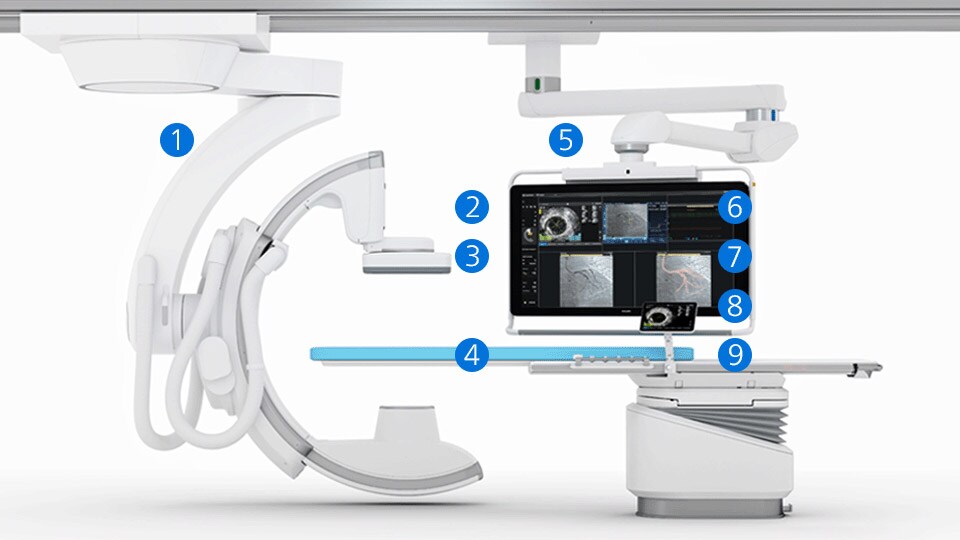

CardiacSwing

A dual-axis rotational system allows you to see comprehensive views of the coronary anatomy, including views often hidden during conventional angiography.

IVUS

Intravascular ultrasound (IVUS) provides images from within the vessel to accurately assess and optimize your treatment plan.

IVUS co-registration

Software helps you understand precisely where the disease begins and ends and guides your pre-and post-strategy decisions for improved outcomes.

Device detection

Enhanced stent visualization quickly verifies positioning before and after deploying balloons and stents.

IntraSight

An interventional applications workspace that brings physiology, imaging and angiographic guidance tools together to optimize treatment plans.

iFR

Only Philips instant-wave free radio (iFR) has co-registration for advanced physiologic guidance, allowing you to precisely determine lesion location and severity.

iFR Co-registration

As an alternative or adjunct to IVUS Co-registration, iFR pullback can be co-registered onto the angiogram to assess both the degree and length of vessel stenosis.

Dynamic Coronary Roadmap

This Philips-exclusive technology provides a real-time view of the coronary arteries and removes the need for additional contrast injections.

StentBoost

This simple, quick and cost-effective tool enhances stent visualization in the coronary arteries.